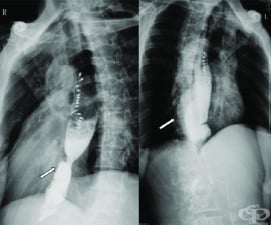

АКЦЕНТИ ОТ РУБРИКА КОНТРАСТНО ИЗСЛЕДВАНЕ НА ХРАНОСМИЛАТЕЛНИЯ ТРАКТ

АКТУАЛНО ОТ РУБРИКА КОНТРАСТНО ИЗСЛЕДВАНЕ НА ХРАНОСМИЛАТЕЛНИЯ ТРАКТ